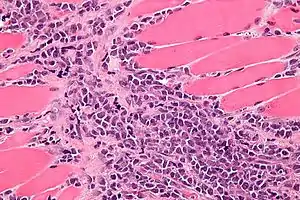

Micrograph of a myeloid sarcoma within muscle. H&E stain.

A myeloid sarcoma (chloroma, granulocytic sarcoma,[1]:744 extramedullary myeloid tumor), is a solid tumor composed of immature white blood cells[2] called myeloblasts. A chloroma is an extramedullary manifestation of acute myeloid leukemia; in other words, it is a solid collection of leukemic cells occurring outside of the bone marrow.